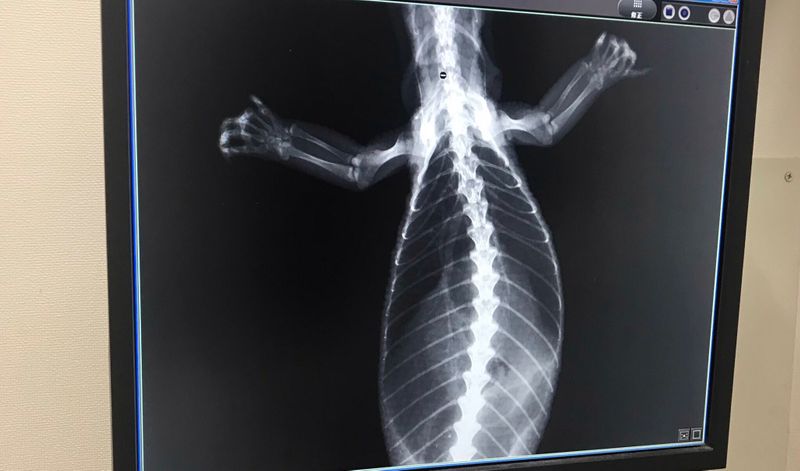

ケージとトカゲを預けて、レントゲンをしてもいました。すぐに帰ってきました。

レントゲン写真と共に、採血結果が出ていました。

痩せている以外特に問題なし。骨密度は採血でしっかり確認出来るので、採血結果へ

トカゲの骨。テンション上がって撮影させてもえました。